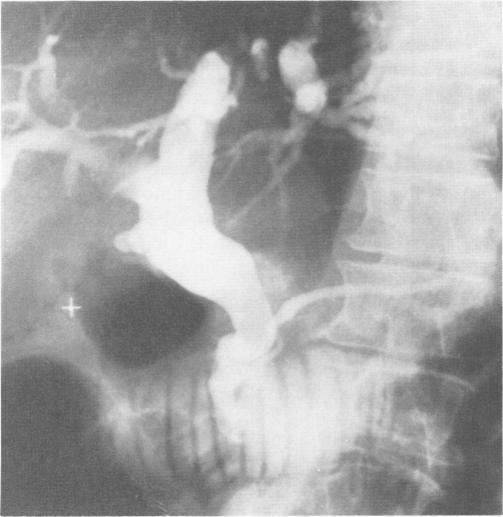

原发性胆总管结石

Primary common duct stones.

Thirty patients were identified as having primary common duct stones. Criteria for diagnosis included at least a two year symptom free interval following cholecystectomy; soft, light brown stones or sludge present in the common duct; and the absence of a long cystic duct remnant or a biliary stricture from the previous surgery. The average age of the 30 patients was 66 years. The interval between cholecystectomy and the diagnosis of primary common duct stones averaged 12 years. Acute cholangitis was a frequent mode of presentation. At the time of surgery the bile duct was often dilated out of proportion to the serum bilirubin. In only one of the 30 patients was ampullary stenosis present. Twenty-six of the 30 patients had only stone extraction and insertion of a T tube for treatment of their primary common duct stones. Twenty-two of the 26 were followed for an average of four years and nine months with no evidence of recurrent stones in 82% (18/22). Four developed recurrent primary common duct stones one, five, five, and 7 years later. It is concluded that most patients with primary common duct stones do well after stone extraction alone.

摘要